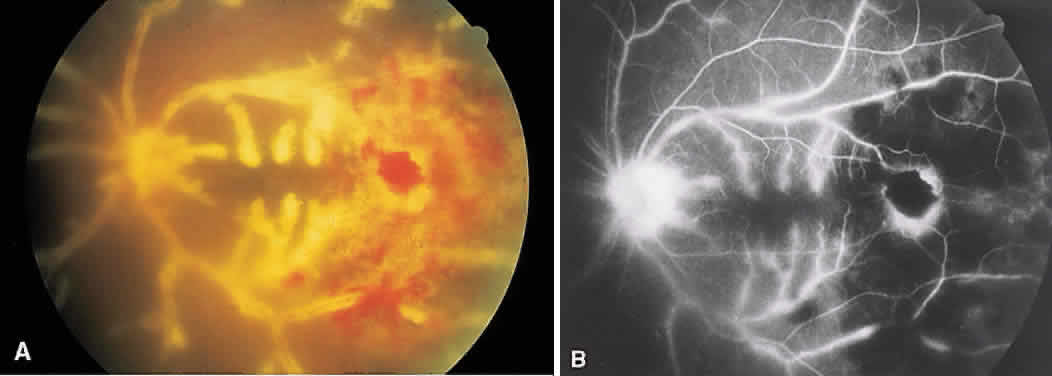

BEHÇET'S DISEASE

Behçet's disease is a systemic occlusive vasculitis that presents predominately in young middle Eastern and Japanese men. The classic features include acute hypopyon, iritis, aphthous stomatitis, and genital ulceration. Skin lesions and strokes also occur frequently. There often is an acute recurrent bilateral panuveitis. Ocular findings include retinal vasculitis (Fig. 6A) with an occlusive arteritis, vitritis, macular edema, ischemic retinitis, ischemic optic neuropathy, peripheral neovascularization, and occasionally SRNV.

Fig. 6. Behçet's disease. A. Fundus photograph showing vasculitis of the superotemporal vascular arcade. Intraretinal hemorrhages also are seen. B. Fluorescein staining of the vessel wall and adjacent areas of blocked fluorescence corresponding to the intraretinal hemorrhage.

On fluorescein angiography (see Fig. 6B), during the active phases of the disease, capillary dropout and dilated retinal capillaries are seen. Dilated retinal capillaries (particularly peripapillary capillaries) leak dye and cause retinal and disc staining.19 Cystoid macular edema,19 SRNV, and disciform scars often are seen.20 Leakage of peripheral capillaries can be seen in patients with normal-appearing fundi.21

ICG angiography shows hyperfluorescent spots from the early to late phases and hypofluorescent plaques, both of which are not evident on FA. Staining of choroidal vessel walls and leakage of ICG from the choroidal vessels also have been described.22–24